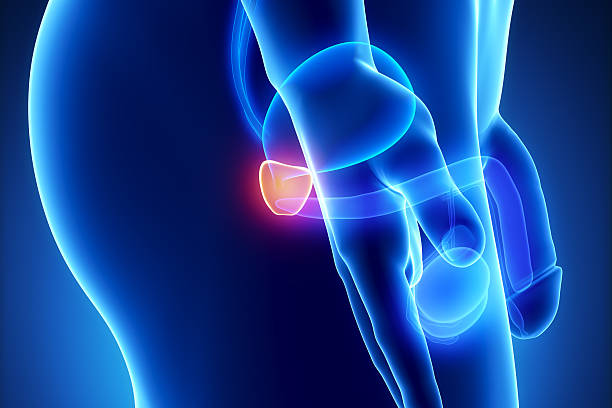

남성 생식기의 요로계와 직접적 연관이 있는 전립선은 사과 모양으로 배꼽 아래쪽에 위치해 있으며 상당히 중요한 역할을 하고 있습니다. 전립선은 사정을 조절하고, 정자의 움직임을 돕는 전립선 분비액을 만들어냅니다. 이 분비액은 정자의 영양 공급과 이동에 필수적인 성분을 포함하고 있습니다. 또한, 전립선은 방광을 둘러싸고 있는 방광 경화근과 골반 바닥 근육에 대한 지지 구조 역할을 할 수 있어 상당히 중요하나 전립선에도 암이 발병될 수 있어 초기에 원활한 대응을 해야만 합니다. 그럼 이번 시간에는 전립선암 초기증상에 대해 자세히 정리해보겠습니다.

3 성기 문제

전립선암은 남성의 생식기와 관련된 문제를 유발할 수 있습니다. 이러한 증상은 성적 욕구의 감소, 성기의 감각이 둔해지거나 성기의 기능이 감소하는 것 등이 있을 수 있습니다.